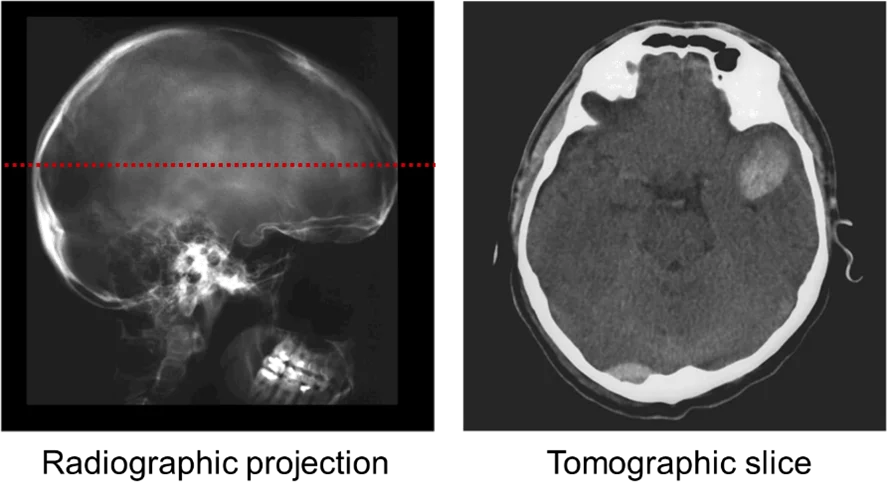

Radiographic projections, however, only provide 2D cumulative information of the structure along the beam path. From a single radiographic projection (Fig. 1, left), it is not possible to determine whether the beam was mostly attenuated when entering or exiting the sample, or maybe homogeneously along its trajectory through the sample. 3D internal structural details (Fig. 1, right) can be revealed by taking radiographs at different sample orientations and combining those using sophisticated mathematical algorithms for tomographic reconstructions based on Fourier analysis (e.g., filtered back-projection) or iterative methods.

Figure 1. (Left) An X-ray radiograph showing a 2D projection the sample’s X-ray absorption. (Right) A reconstructed tomographic slice across the red dashed line indicated on the left. A collection of tomographic slices along the full height of the radiograph on the left constitutes a 3D map of the sample’s X-ray absorption. (Source: )